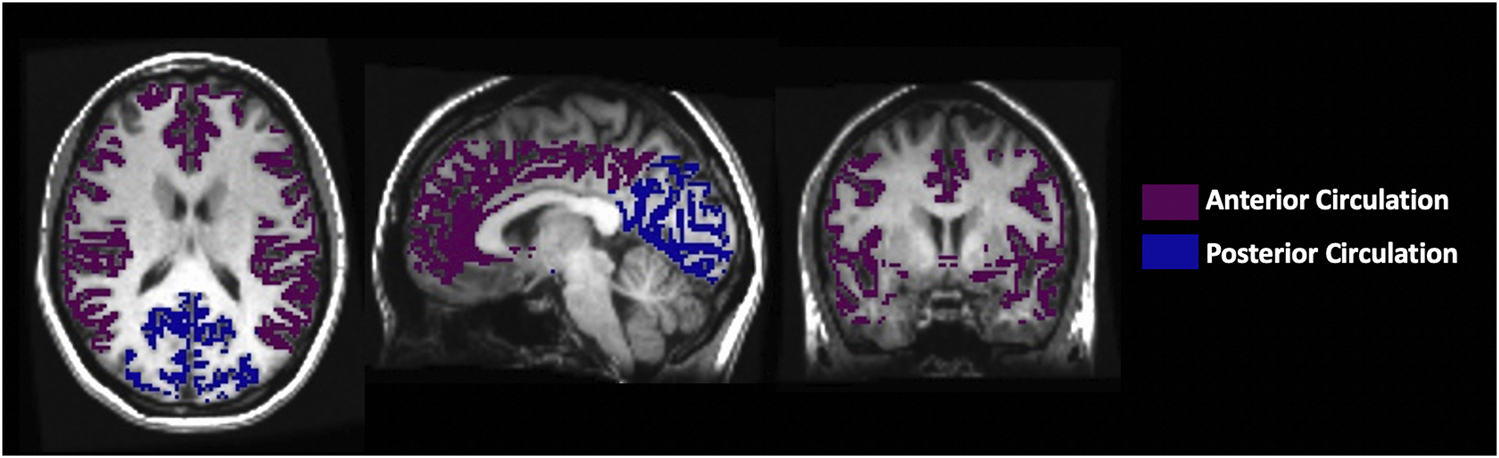

Maps of the perfusion metrics obtained from each analysis were transformed into Montreal Neurological Institute (MNI) space and overlayed onto their respective anatomical images. Analytical processing software, SPM8 (Wellcome Department of Imaging Neuroscience, Institute of Neurology, University College, London, UK), was used to segment the anatomical images (T1 weighted) into grey matter (GM) and white matter (WM). The vascular regions of interest (middle cerebral artery (MCA), posterior cerebral artery (PCA) and anterior cerebral artery (ACA)) were previously delineated manually on an anatomical MNI template. For this analysis, the supratentorial cortical grey matter MCA and ACA were combined as the anterior circulation mask and the supratentorial cortical grey matter PCA was used as the posterior circulation mask, as shown in Figure 3.

FIGURE 3. The axial, sagittal and coronal view of the manually delineated grey matter in the anterior and posterior circulation.